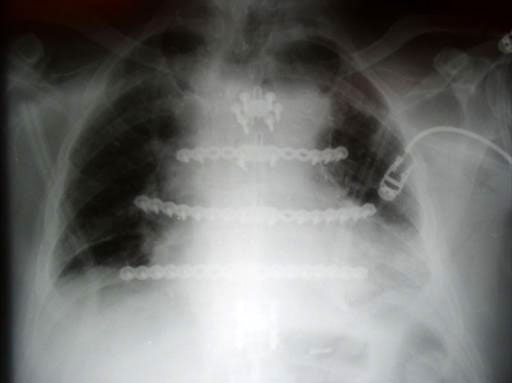

While many surgeons currently remove the sternum the new system allows for a procedure that involves reducing the sternal halves and implanting plates, which span the sternum and are fixed to the ribs and/or sternum of the patient. The chest wall is then reinforced through advancement of the pectoral muscles.

The Sternal Fixation System consists of titanium locking plates that function with 3.0 mm titanium locking screws, similar to those used in the mandible area. The straight plates are actually an assembly of two single plates, which are connected by a U shaped pin. In case of emergency removing the pin allows re-entry into the thoracic cavity. Long and straight plates are fixed to the ribs; additional smaller plates are available for fixation of the manubrium.

The Sternal Fixation System is available with 12-hole Titanium Locking Plates (Fig 2) as well as Titanium Locking H plates small/large and Titanium Locking Star Plates with 6 and 12 holes (Fig 3). The set contains Locking Screws (3.0 mm) from 8 mm to 18 mm and the Titanium Emergency Release Pin to connect and disconnect the plates at the fixation site,

A Titanium Sternal Locking Plate with 30 holes is available additionally (Fig 2).

Sternal closure with Ti Plate system

Cases provided by J Thornton, UT Southwestern Medical Center, Dallas, TX